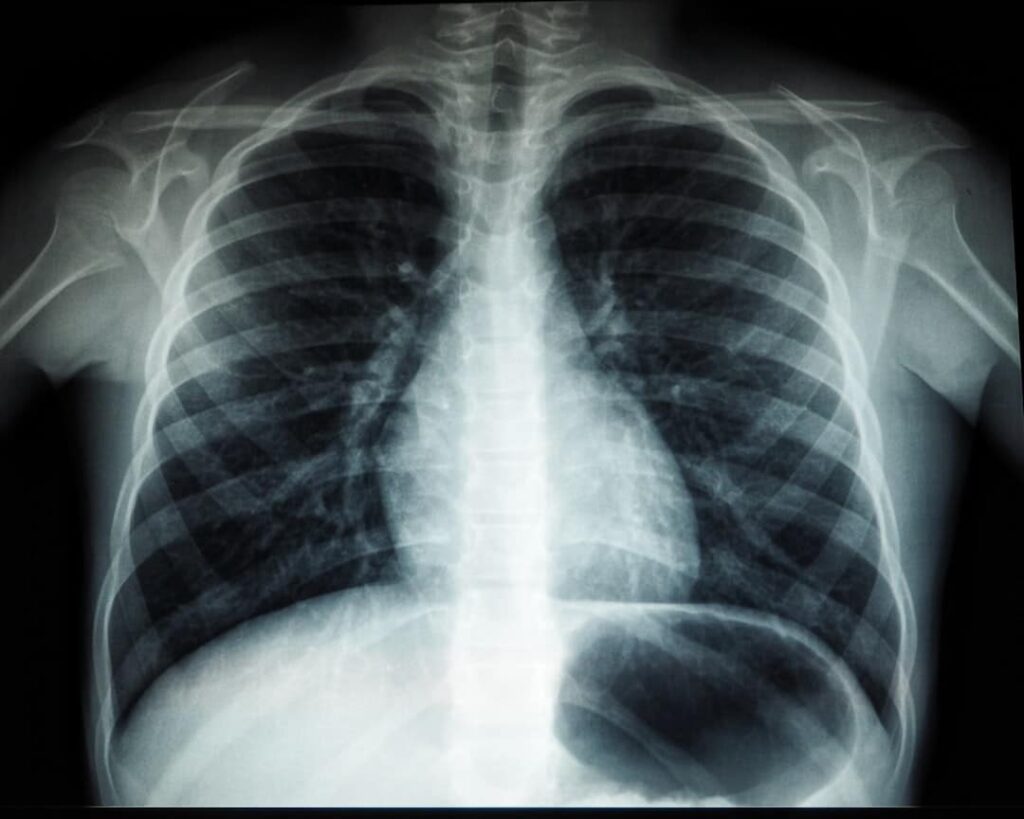

Pulmão de Soldador (Siderose Pulmonar): Direito das Vítimas

Foi diagnosticado com pulmão de soldador (siderose)? Descubra seus direitos junto ao INSS e à empresa e saiba como buscar indenização.